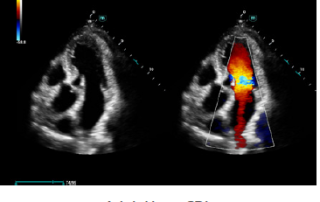

Mindray Ultrasound Consona N9